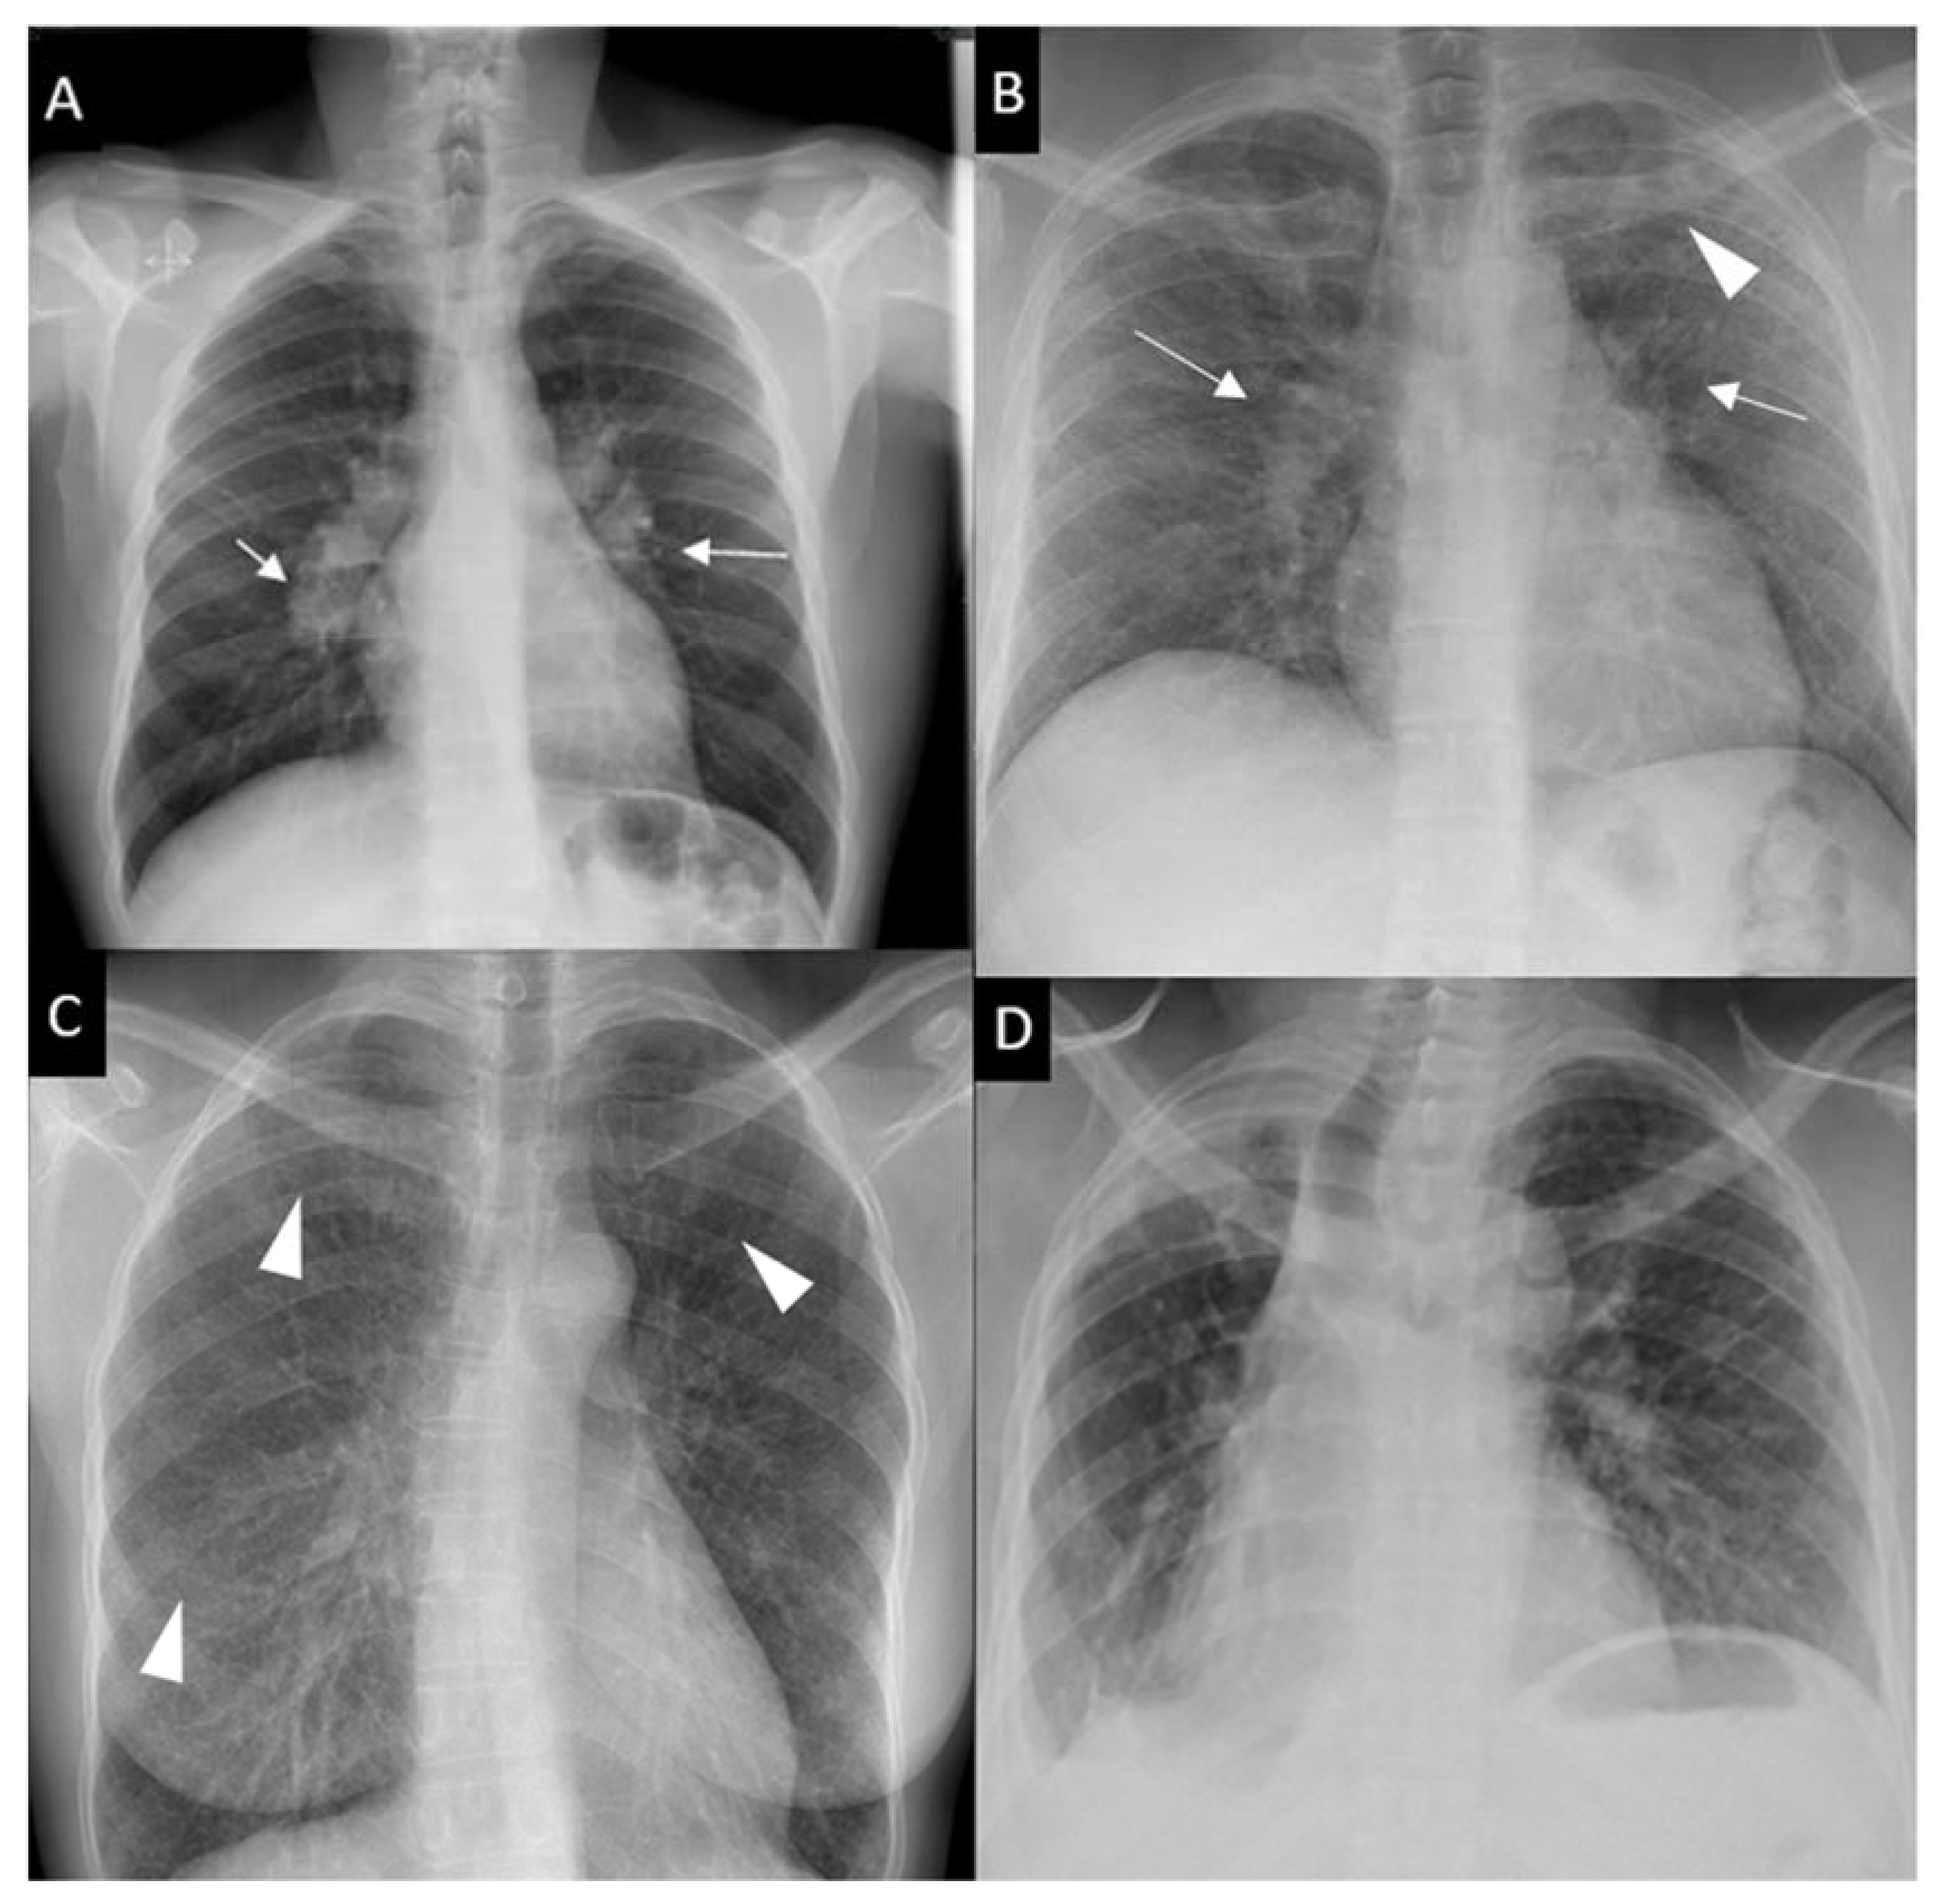

Respiratory symptoms are found at presentation in 30–53% of patients; cough in 27–53%, dyspnea in 18–51% and chest pain in 9–23% [16,30,31]. Chronic dyspnea is most frequently seen in patients with a delayed diagnosis, such as in the 10% of patients diagnosed with sarcoidosis-related lung fibrosis [9]. Bilateral perihilar lymphadenopathy, which is most frequently mediastinal lymphadenopathy [32] and perilymphatic pulmonary nodules predominantly seen in the upper lobe are the most typical imaging findings. Scadding’s classification defines five stages of sarcoidosis on a CXR (Figure 1).

Figure 1.

Chest x-ray (CXR) staging system. Stage 0-normal CXR (not shown); (A) Stage 1-bilateral hilar lymphadenopathy (white arrows); (B) Stage 2-bilateral hilar lymphadenopathy (white arrows) and pulmonary infiltrates in upper lobes (white arrowhead); (C) Stage 3-pulmonary infiltrates (white arrowhead) without bilateral hilar lymphadenopathy; (D) Stage 4-pulmonary fibrosis.